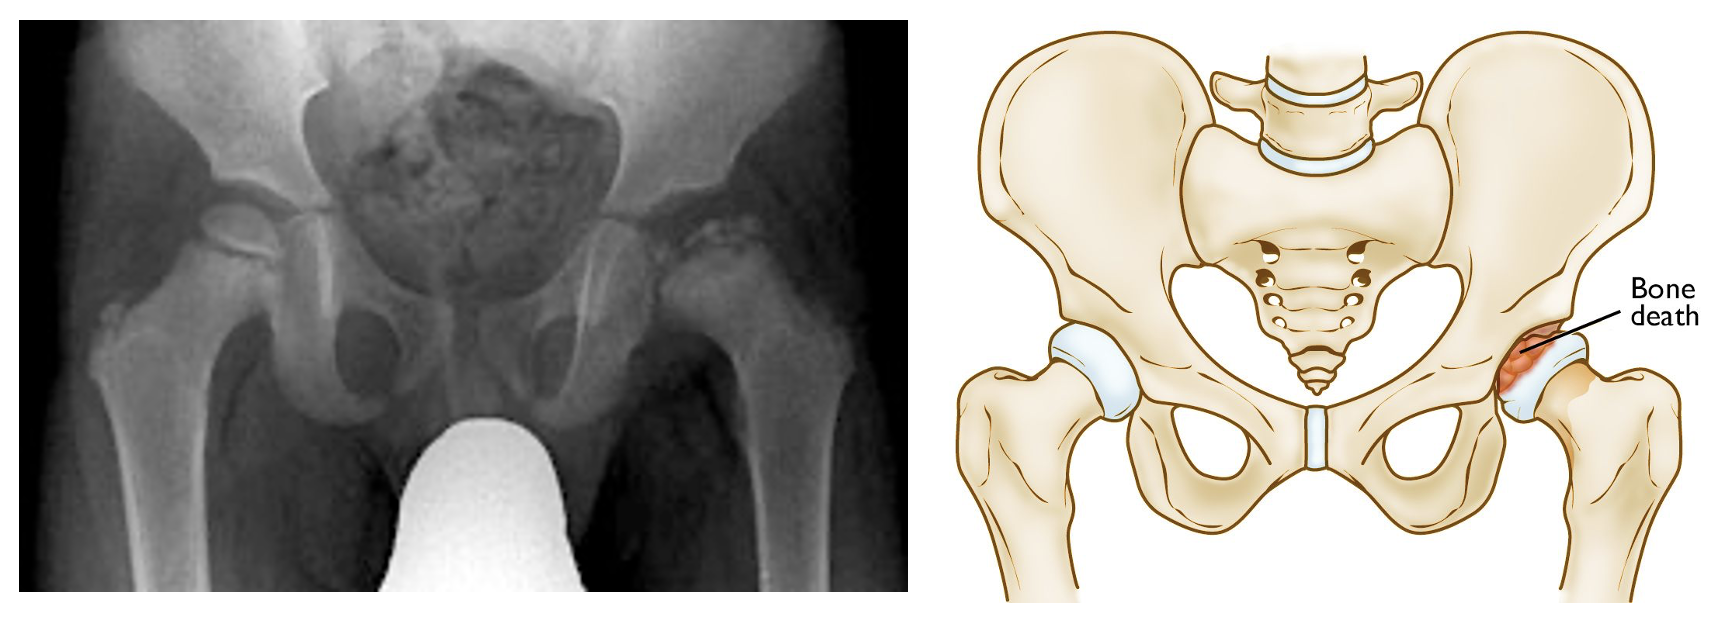

• 정의: 성장기 아동의 대퇴골두 골단(epiphysis)으로 가는 혈류 장애로 인한 특발성 무혈성 괴사(Idiopathic AVN)

• X-ray (AP & Frog-leg view):

• 초기 (Initial): 정상 또는 관절 간격 확장 (medial joint space widening)

• 괴사기 (Fragmentation): 골두 분절화, 편평화 (Coxa plana), 골두 경화 (Sclerosis)

• 재형성기 (Re-ossification): 새로운 골 형성